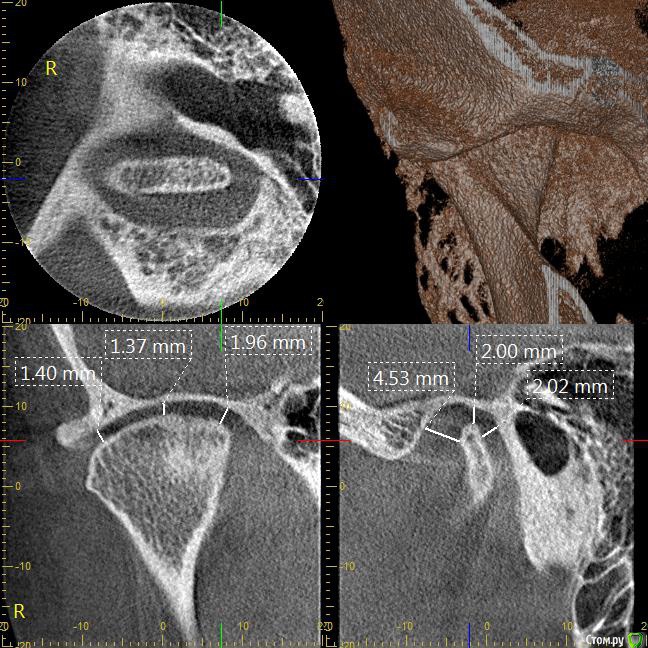

Мне 31 год. В детстве мне выбили верхний зуб 2-ку. Собираюсь лечиться брекетами, а потом вставлять имплант на место двойки. Но у меня есть еще проблеми с ВНЧС (с детства болит, хруст, щелчки), делала недавно КТ ВНЧС, диагноз артрит или артроз. Ходила к многим специалистам, все говорят разное. Надо ли проводить лечения капой моей дисфункции ВНЧС до установки брекетов или после установки брекетов?